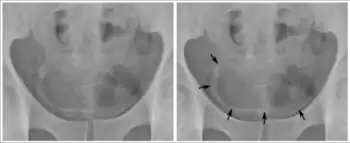

Orina

El examen de orina se recomienda sólo para S. haematobium. Una vez centrifugada la muestra de orina, el sedimento resultante se filtra con membranas Nucleopore ® y se procede al recuento de huevos sobre la misma. El diagnóstico puede complementarse con los rayos X de la zona pélvica, con el fin de localizar calcificaciones típicas de una infección crónica.